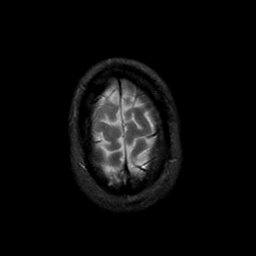

MR Study #23, January 26, 1992 -- Slice #45